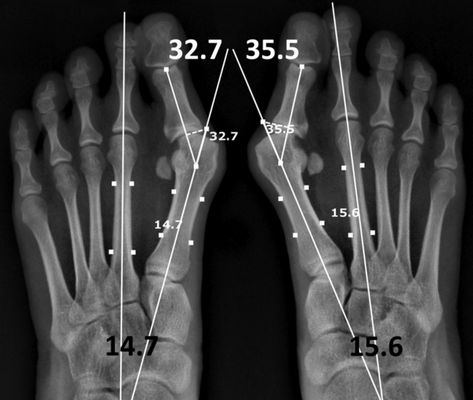

Диагностика повреждений сустава Лисфранка.

Диагностика повреждений сустава Лисфранка сложная задача, которая требует от ортопедического хирурга высокого уровня квалификации и настороженности. До 25 % случаев пропускается при первичном обращении пациента.

Симптомами повреждения сустава Лисфранка являются боль в области переднего и среднего отделов стопы, усиливающаяся при осевой нагрузке. При осмотре определяется кровоподтёк, чаще по подошвенной поверхности, в проекции сустава Лисфранка.

При значительном смещении может быть заметна грубая деформация. Отёк диффузно распространяется по всей стопе. Боль при пальпации в проекции связки Лисфранка.

Для полноценной клинической диагностики переломовывиха в суставе Лисфранка нельзя обойтись без оценки степени нестабильности. Для проведения данных тестов необходима адекватная анестезия. Для выполнения теста захватите 2-5-ую плюсневые кости пальцами одной руки, пальцами другой пальпируйте область сустава Лисфранка с тыльной стороны. При смещении плюсневых костей (второй плюсневой кости) к тылу определяется соответственно тыльная нестабильность, если возможно смещение кнутри или кнаружи, это является признаком тотальной нестабильности и является показанием к оперативному лечению.

Для инструментальной диагностики используются рентгенограммы с\без нагрузки в сравнении со здоровой стороной, при их малой информативности рекомендовано выполнение стресс-рентгенограмм, аналогично приведёному выше тесту на нестабильность.

При рентгенографии все снимки выполняются в сравнении со здоровой стопой. Существует несколько основных рентгенологических признаков повреждения сустава Лисфранка. 1. Отсутствие параллельности медиального края основания 2-й плюсневой и медиального края медиальной клиновидной кости 2. Расширение между основаниями 1 и 2 плюсневых костей 3. Наличие костного фрагмента в области основания 2-1 плюсневой кости 4. Тыльный подвывих на боковой проекции 5. Разрыв линии предплюсне-плюсневого сочленения.

В сложных с диагностической точки зрения случаях целесообразно использование КТ и МРТ.